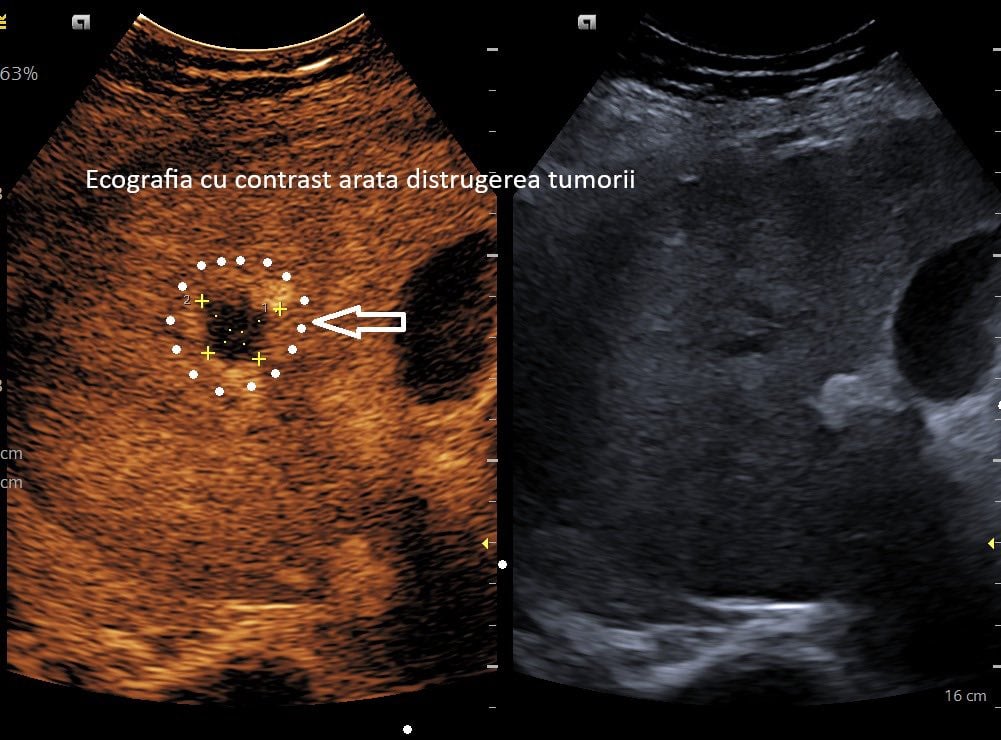

Spitalul Județean Craiova anunță realizarea primei ablații cu microunde a unei tumori hepatice. La o lună după procedură, investigațiile imagistice au demonstrat că tumora a fost complet distrusă.

Reprezentanții spitalului au menționat că, după o lună, examenele imagistice au confirmat eliminarea completă a celulei tumorale.